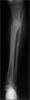

Progress

Deformity corrected with 150degrees knee motion